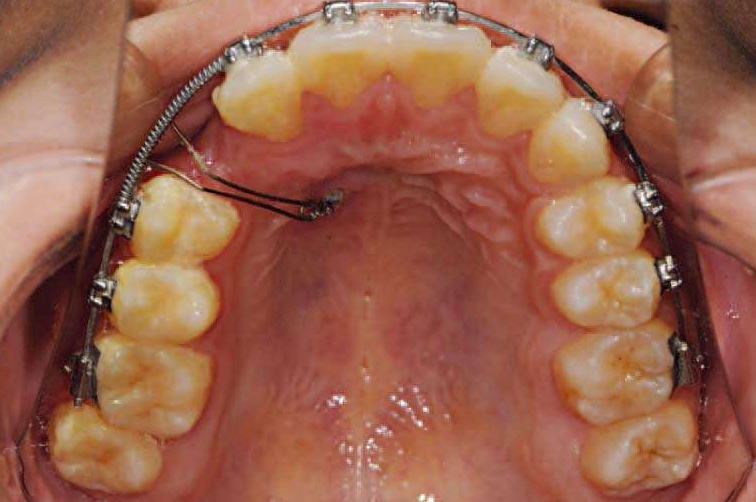

图7 埋伏尖牙使用Ballista弹簧牵引

图8 埋伏尖牙使用Ballista弹簧牵引